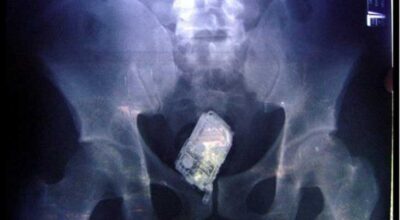

Esta recopilación de imágenes recoge alguna de las situaciones más estrambóticas que se han podido dar en una sala de rayos X. Todas ellas tienen algo en común: Son objetos extraños para el cuerpo humano que, de alguna manera han encontrado una vía de entrada, pero se han perdido a la hora de encontrar la de salida.

Muñecas de juguete descabezadas, botellas, armas, frascos, botes de plástico, teléfonos y hasta una cinta de casete pueden encontrarse en esa suerte de “punto limpio” al que ha quedado reducido el interior de los afectados.

No sabemos, ni juzgamos, la forma o los motivos por los que terminaron atrapados en dichas partes del cuerpo, pero estamos convencidos de que algún doctor estuvo al borde de la carcajada cuando se encontró con casos tan llamativos e inverosímiles como estos ¡Ver para creer!